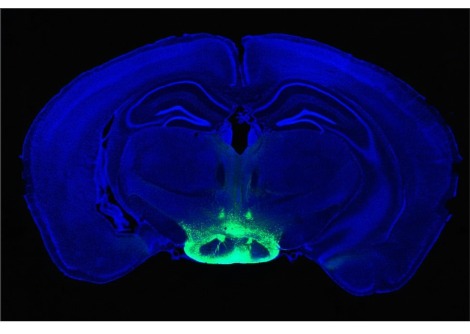

توصّل سيث وفريقه لهذه النتيجة من خلال إعادة تحليل البيانات التي جمعها الباحثون سابقا في كلية إمبريال في لندن. رصد "روبن كارهارت-هاريس" وزملاؤه نشاط المخ في 19 متطوعا ممن تناولوا الكيتامين وهو دواء يستخدم في تخدير الحيوانات في الطب البيطري وللتخدير في العمليات الجراحية للأطفال وفي الجراحات الميدانية، و 15 متطوّعاً من الذين تناولوا "ثنائي إيثيل أميد حمض الليسرجيك" LSD وهو مادة صلبة عديمة اللون والرائحة والطعم ويعد من المهلوسات القوية المؤثرة على العقل، و 14متطوعاً ممن كانوا تحت تأثير"البسيلوسيبين" وهو مركب للهلوسة موجود في الفطر السحري. استخدم فريق كارهارت-هاريس مجموعات من أجهزة الاستشعار الموصولة بالجمجمة لقياس المجالات المغناطيسية التي تنتجها خلايا المتطوّعين العصبية ومقارنتها مع المتطوّعين الذين أخذوا المخدّر الوهمي.

يقول سيث والذي عمل فريقه مع كارهارت-هاريس على إعادة التحليل: "أخذنا البيانات المتعلّقة بنشاط الدماغ وتأكدنا من جودتها ثمّ قمنا بتقسيمها إلى مجموعات تبلغ كلّ مجموعة مدّة ثانيتين بحيث قمنا بقياس التنوّع في كلّ مجموعة".

أظهرت الأبحاث السابقة أنه عندما يكون النّاس في حالة اليقظة تكون لديهم أنماطاً من نشاط الدماغ أكثر تنوعا مقارنة بالنّاس النائمين. وجد فريق سيث أن الأشخاص الذين تناولوا المخدر المخل بالنفس وهي مخدرات نفسية التأثير تقوم أساساً على تحويل الإدراك والاستيعاب و ذلك عبر مقابلة مستقبلات السيروتونين يظهرون تنوعا أكبر في النشاط الدماغي حيث يصل هذا المستوى لأعلى المستويات التي تمّ قياسها على الإطلاق.